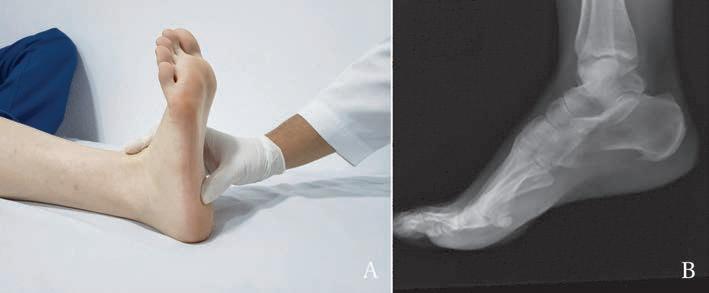

Lafascitisplantarcorrespondealainflamacióndelaaponeurosisquenaceenelcalcáneoofasciaplantar.Típicamentesepresentacomoundolor enlaplantadelpie,enlazonadeltalón—o talalgiadepredominiomatutino—,condolorenelprimerpasodelamañana.Seconsideraunainflamaciónporsobreusoyescomúnenatletas,poblaciónobesaysedentaria. Tieneunaasociaciónaparenteconlaboresqueimplicanposicionesbípedasprolongadasotiemposlargosdemarcha.Elmicrotraumarepetitivo generaunaperiostitisenelsitiodeinserciónenelcalcáneo.Clínicamente seevalúaconlapalpacióndeltalónenelsitiodeinsercióndelafasciaen elcalcáneoyeldolorempeoraconlaflexióndorsaldelpie.

Esdeanotarqueenlaimagenderadiografíalateralseevidenciaunaapofisitisdelcalcáneooespolóncalcáneo,elcualsecreíaqueeralacausadel dolorplantar(figura45).Estateoríahasidorefutadaporlaliteraturaortopédicayhoysesabequeelespolóncalcáneonoserelacionaconeldolor porfascitisplantarnipresentapatologíaalguna,porlocualsedebeinformaralpacientequeestehallazgoradiológiconotienerelevanciaclínica.

Figura 45 Espolóncalcáneo.A)Examenfísicodelafasciaplantar.B)Espolóncalcáneo Fuente: elaboraciónpropia